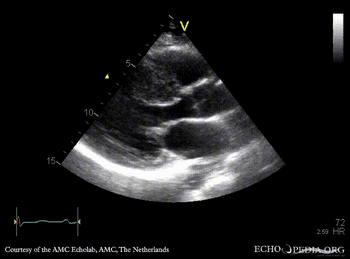

PSAX: severe concentric hypertrophy of left ventricle PLAX with Color Doppler: high velocity turbulent flow in LVOT, moderate mitral regurgitation